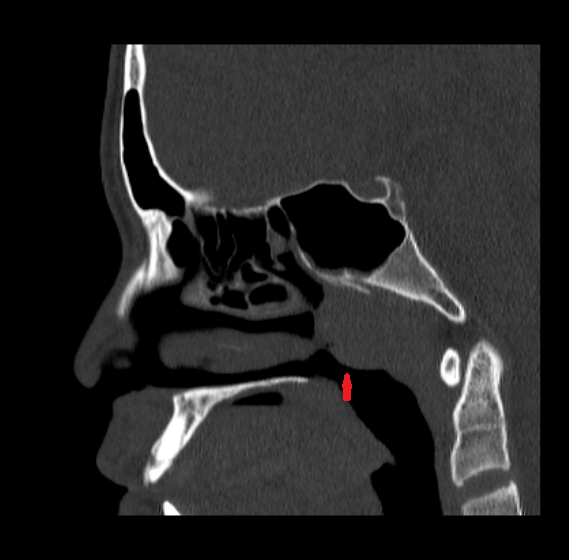

临床中,腺样体肥大的诊断并不复杂。通过鼻咽侧位片或电子鼻咽镜检查,可直观观察腺样体大小及阻塞程度;鼻阻力检测则能量化评估鼻腔通气功能,为治疗决策提供客观依据。对于症状较轻的患儿,医生可能建议使用鼻用糖皮质激素等药物缓解炎症;但当出现重度鼻阻塞、睡眠呼吸暂停、反复发作的中耳炎或鼻窦炎时,手术切除肥大的腺样体成为必要选择。目前,低温等离子腺样体切除术已成为主流术式,具有创伤小、出血少、恢复快等优势,多数患儿术后2-3天即可出院。

箭头所指就是腺样体